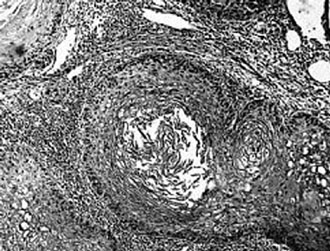

Νέα Υόρκη: Η αντίσταση ινσουλίνης, δεν αποτελεί μια κατάσταση που συντελεί μόνο στην εκδήλωση του διαβήτη, αλλά αποτελεί ένδειξη επικείμενης καρδιακής νόσου, σύμφωνα με αμερικανική μελέτη που δημοσιεύεται στο επιστημονικό έντυπο Hypertension.